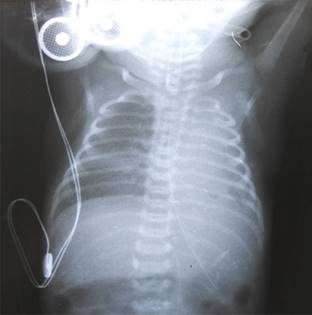

A las 47 h presenta empeoramiento, tanto de su cuadro clínico como en gasometría: pH 6.98, PaCO2 93.0, PaO2 16.0, HCO3 22.4, -EB -11.7. Rx de tórax con incremento del EPI en pulmón izquierdo. Se decidió realizar VS al pulmón contralateral (derecho), dejando en atelectasia total al pulmón izquierdo, además se administró tercera dosis de surfactante pulmonar. Con todo lo anterior, las imágenes reticulonodulares del pulmón derecho presentan mejoría (Figura 2), lo mismo que los datos de dificultad respiratoria.

Figura 2: Radiografía posterior a la ventilación selectiva del pulmón derecho en la que se observa atelectasia total del pulmón izquierdo y mejoría de la radioopacidad reticulonodular por la aplicación de surfactante pulmonar selectivo.